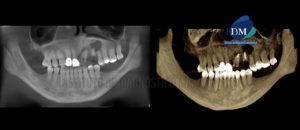

Paciente masculino de 67 años de edad, es referido al Instituto de Diagnóstico Maxilofacial (IDM) para evaluación tomográfica para planificación de implantes dentales. En la